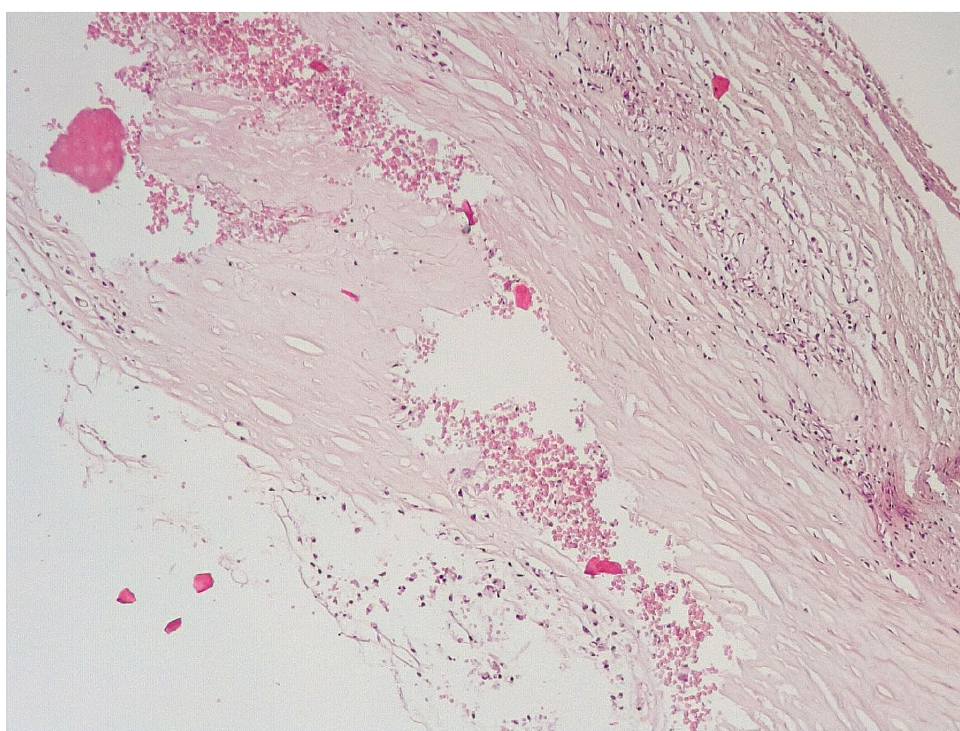

Патоморфологическое исследование стенок КА в ранние сроки после стентирования выявило характерные особенности. В течение первых 3 дней после стентирования в стенке КА имелась атерома с признаками геморрагий. Эндотелий был на большем протяжении разрушен, с признаками десквамации, с окружающей очаговой лейкоцитарной инфильтрацией. Вокруг атеромы, со стороны медии и адвентициальной оболочки, отмечалась умеренновыраженная лимфоцитарная инфильтрация (рис. 1).

Обращало внимание, что в местах «оголенного» эндотелия КА отмечалась слабая экспрессия белка CD31, что указывало на выраженные дистрофические и некробиотические изменения клеток (рис. 2). При этом экспрессия ФВ была яркой, выраженной на всем протяжении интимы КА (рис. 3).

Проведенное морфоиммуногистохимическое исследование КА после стентирования в ранние сроки показало определенные закономерности их поражения. Было показано, что в течение первых 3 дней после стентирования КА в их стенках наблюдаются острые повреждения клеток эндотелия в виде десквамации, дистрофических и некробиотических процессов, внутристеночные геморрагии в зонах локализации атером.

Показано, что после стентирования в течение первых 3 суток в стенках КА вокруг атером встречаются геморрагии, мелкие лейкоцитарные инфильтраты, повреждение клеток эндотелия, что наряду с экспрессией фактора Виллебранда является предиктором для формирования пристеночных тромбов.